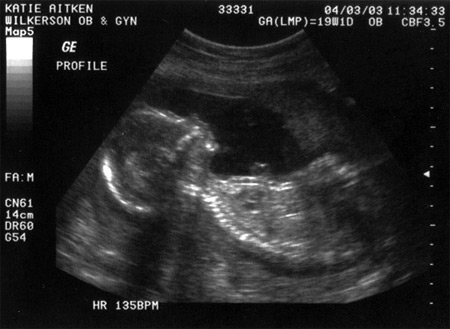

Here is Maeve's sonogram, from when she was the same gestational age: